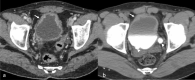

The purpose is to discuss abdominal tuberculosis mimicking malignancy involving the abdominal viscera. TB of the abdominal viscera is common, especially in countries where tuberculosis is endemic and in pockets of non-endemic countries. Diagnosis is challenging as clinical presentations are often non-specific. Tissue sampling may be necessary for definitive diagnosis. Awareness of the early and late disease imaging appearances of abdominal tuberculosis involving the viscera that can mimic malignancy can aid detecting TB, providing a differential diagnosis, assessing extent of spread, guiding biopsy, and evaluating response.